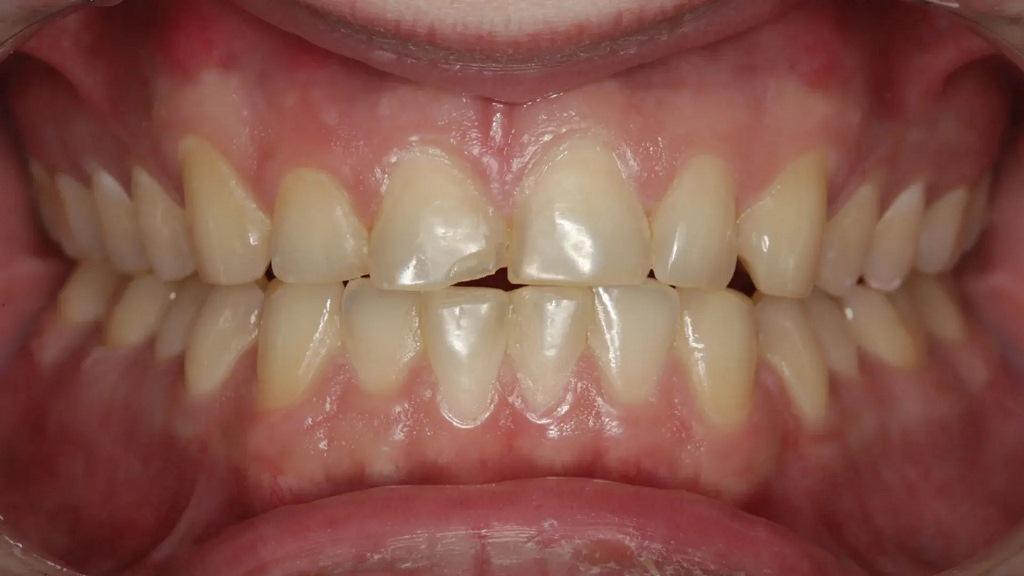

Пациент обратился со сколом композитной реставрации IV класса на зубе 11 по причине дефекта (фото 1). За последний год проводили реставрацию трижды и она снова скалывалась. Было ли это из-за плохой техники или по причине некачественных материалов? Более чем вероятно, что это произошло из-за окклюзии. Помимо большого количества композита на лицевой поверхности, который выходил за пределы области скола, большая часть небной поверхности зуба была стерта до дентина из-за гиперфункции при протрузии и боковом перемещении в течение многих лет, что создавало для пациента функциональную и эстетическую дилемму. «Консервативный» подход, возможно, заключался в том, чтобы снова заклеить зуб композитом и надеяться на лучшее. Однако, возможно, это был не самый лучший долгосрочный подход, учитывая функциональную нагрузку в этой области, даже при наилучшем выравнивании зубов. В конце концов, насколько консервативно постоянное воздействие на зуб вращающимися инструментами для фиксации композита, который продолжает разрушаться?

Фото 1: Предоперационный снимок лицевой стороны реставрации из композитного материала со сколом на зубе 11 в максимально сжатом положении.